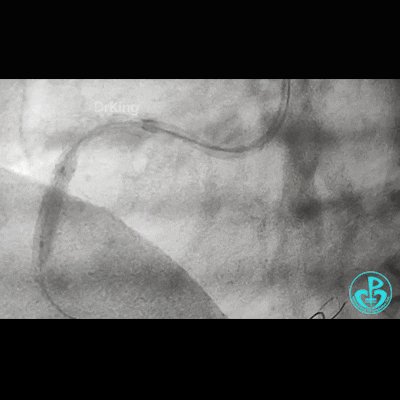

冠脉造影

右锁骨下动脉迂曲打圈,影像如下:

病变简单吧!